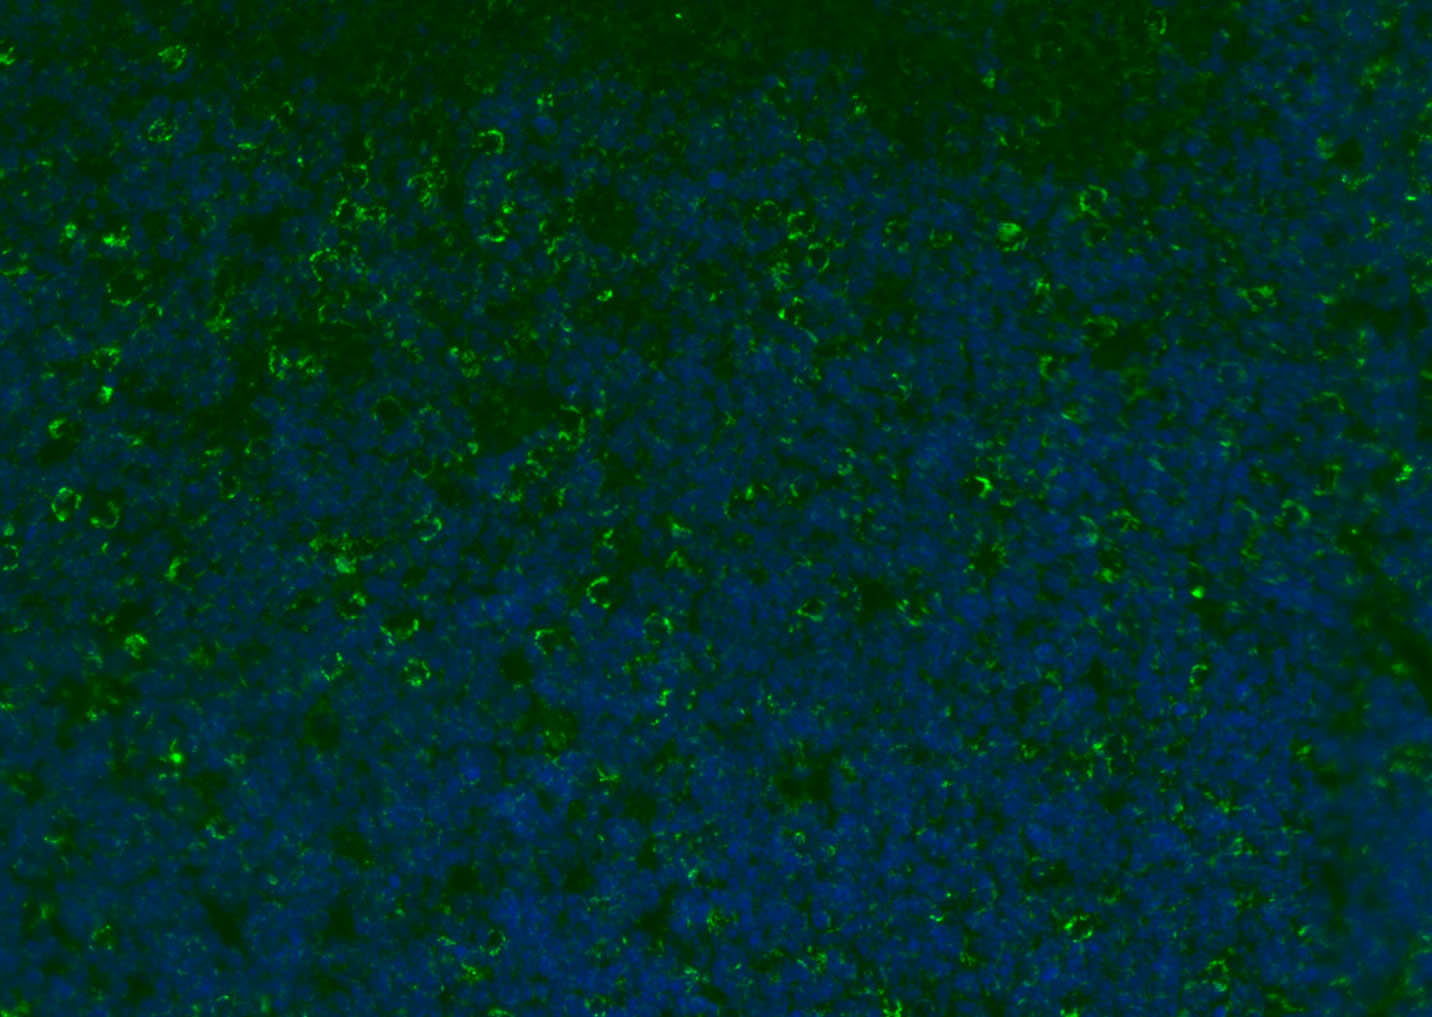

Paraformaldehyde-fixed, paraffin embedded (mouse lymphoid); Antigen retrieval by boiling in sodium citrate buffer (pH6.0) for 15min; Blocking buffer (normal goat serum) at 37°C for 30min; Antibody incubation with (CD8B) Polyclonal Antibody, Unconjugated (bs-4914R) at 1:200 overnight at 4°C, followed by a conjugated Goat Anti-Rabbit IgG antibody (bs-0295G-FITC) for 90 minutes, and DAPI for nuclei staining.